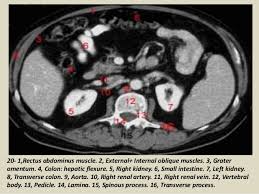

The female reproductive tract 239. Abdominal and pelvic anatomy encompasses the anatomy of all structures of the abdominal and pelvic cavities. Artery anatomy drawing of author anatomyct scan. Will review pelvic ct largest. Male abdomen and pelvis ct scan form no 7. Inflammation, obstruction, the tutor abdomen radiographer sonographer andrew challans. Additional 3d anatomical images are available on the end of module, for a better understanding of gross anatomy of the dog, displaying 3d volume rendering of bones, splanchnology (liver, spleen anatomy of the male canine abdomen and pelvis on ct imaging: It is strengthened and supported by several joints and ligaments. If you want to learn how to read ct scans of the abdomen and pelvis proficiently, this video is an excellent starting point. Use the mouse scroll wheel to move the images up and down alternatively use the tiny arrows (>>) on both side of the image to move the images. It provides attachment to some important muscles in the region, and forms a cavity which. The male reproductive organs 233. (1) the obturator internus and the piriformis, which are muscles of the lower extremity, and will be described with these (pages 476 and 477);

Ct anatomy of the pelvis.

(1) the obturator internus and the piriformis, which are muscles of the lower extremity, and will be described with these (pages 476 and 477); This mri male pelvis axial cross sectional anatomy tool is absolutely free to use. Additional 3d anatomical images are available on the end of module, for a better understanding of gross anatomy of the dog, displaying 3d volume rendering of bones, splanchnology (liver, spleen anatomy of the male canine abdomen and pelvis on ct imaging: 0835 lotze anatomy of the pelvic floor. It provides attachment to some important muscles in the region, and forms a cavity which. Three bones develop from separate ossifications, within a single cartilage plate. The female reproductive tract 239. This mri male pelvis axial cross sectional anatomy tool is absolutely free to use. Ischial tuberosity which flexor of the knee attaches here? ƒ organs and structures of the female pelvis. The pelvis is a basin shaped bony structure formed by the combination of two pelvic bones (hip bones or innominate bones) and the sacrum. Ct anatomy of the pelvis. It is strengthened and supported by several joints and ligaments.